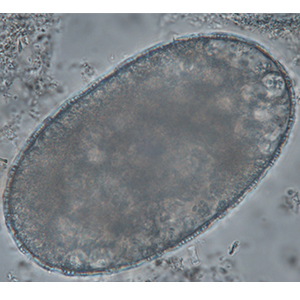

Fasciolopsis buski eggs are operculated and large (130-140 µm long and 80-85µm large). Their content is granulomatous (Garcia, 2021).